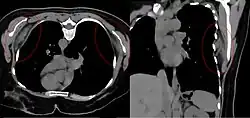

Bilateral elastofibroma dorsi in native computed tomography: left image axial in prone position (for biopsy), right image oblique coronal view.

By computed tomography, there is a poorly circumscribed, heterogeneous soft tissue mass, with a signal intensity similar to skeletal muscle. The fact that the lesion may be bilateral, helps eliminate a sarcoma from further consideration.[6] At US, elastofibromas are depicted deep to the musculature as a multilayered pattern of hypoechoic linear areas of fat deposition intermixed with echogenic fibroelastic tissue.[7] The mass often protrudes from the subscapular region upon shoulder abduction, allowing better delineation of the finding.[8]